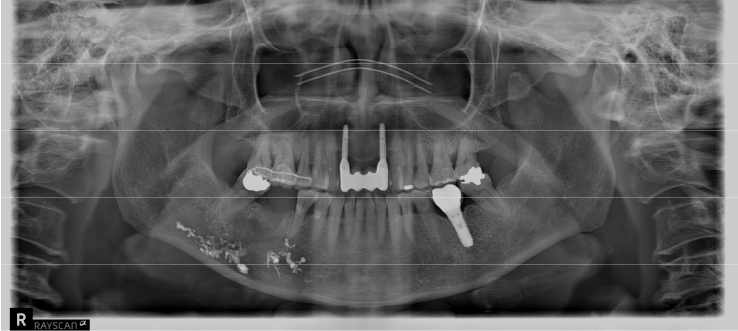

A 63-year-old female presented three days after endodontic treatment of the mandibular left second molar (#37) with symptoms of numbness in the left lower lip and gingiva. A panoramic radiograph and cone-beam computed tomography (CBCT) revealed extrusion of Calcipex II into the mandibular canal (Fig. 1). Initial neurosensory testing demonstrated mild hypoesthesia. She was admitted for foreign body removal and neurorrhaphy under general anesthesia. A post-operative panoramic radiograph confirmed the removal of the foreign body (Fig. 2). Although surgical curettage and neurorrhaphy were performed on the fourth day post-onset, no significant symptom relief was noted at the one- and two-week follow-ups. At the three-month follow-up, she reported persistent numbness with mild neuropathic discomfort but no marked improvement. A follow-up neurosensory exam is scheduled for the six-month check-up.

Figure 1.

A. Pre-op panoramic radiograph of Case 1 patient. B. Pre-op CBCT of Case 1 patient